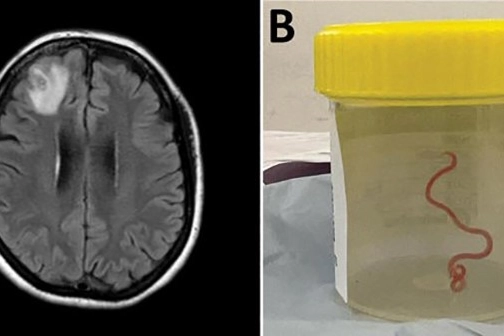

Avustralya Ulusal Üniversitesi’nden (ANU) yapılan açıklamaya göre 64 yaşındaki bir kadın karın ağrısı, ishal, kuru öksürük, ateş ve geceleri terleme şikayetleriyle ilk olarak Ocak 2021'in sonlarında hastaneye kaldırıldı. Daha sonra 2022 yılında unutkanlık ve depresyon şikayetleri de görülen kadın, Canberra Hastanesi'ne sevk edildi. MR taraması yapılan kadının, beyninin sağ ön lobunda anormallik tespit edilmesi üzerine ameliyat kararı verildi. Ameliyat sırasında doktorlar, kadının beyninde 8 santimetre uzunluğunda canlı solucan buldu. Latince adı "Ophidascaris robertsi" olan solucanın normalde piton yılanlarında bulunan bir parazit olduğu belirtildi. ANU ve Canberra Hastanesi'nin önde gelen bulaşıcı hastalık uzmanı Doçent Sanjaya Senanayake, “Bu, dünyada bir insanda görülen ile Ophidascaris vakasıdır” ifadesini kullandı. Yeşillikten bulaştığı düşünülüyor Kadının evinin yakınlarında bir göl olduğu, gölün çevresinde de söz konusu parazitin yaşadığı piton türünün bulunduğu ifade edildi. Pitonun paraziti boşaltım yoluyla attığı, kadının ise gölün yanında bulunan yeşilliklere dokunması ya da topladığı yeşillikleri yemekte kullanması sonucu paraziti vücuduna aldığı belirtildi. Kadının enfeksiyon hastalıkları ve beyin uzmanlarından oluşan ekip tarafından takibi sürüyor.